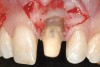

A 27-year-old non-smoking man presented for esthetic enhancement of the left central incisor, which had a pre-existing full-coverage restoration that required replacement (Figure 16). The patient had begun orthodontic treatment in the mandibular arch to correct a minor occlusal imbalance and required coronal repositioning and soft tissue grafting to correct gingival recession at the facial of the right canine, in addition to correction of the free gingival margin at the facial of the left central incisor, which was asymmetrical to the free gingival margin of tooth No. 8. Additionally, the facial gingival tissues were of a thin biotype, which at the facial surface of the left central incisor allowed for the darkened root surface to be visible through the tissue (Figure 16).

The treatment plan was to accomplish an increased zone of keratinized tissue at tooth No. 6, and increase the thickness of the facial tissue at tooth No. 9, in addition to coronally repositioning the free gingival margin. Complicating this treatment plan was the fact that at the facial surface of tooth No. 9, a biologic width invasion was present due to the prepared margin for the pre-existing restoration being placed too close to the facial alveolar crest of bone (the patient had presented to the periodontist with a provisional restoration in place). Any correction to the area would require movement of the facial margin of the tooth in a coronal fashion to re-establish the appropriate distance from the facial height of bone to the margin of the restoration. Additionally, options were given to the patient for harvesting the soft tissue, using connective tissue from the palate, or the use of an acellular dermal matrix graft, which would nullify harvesting tissue from the palate region.

Figure 16  Case Two Preoperative clinical view, maxillary left central incisor.

Figure 16